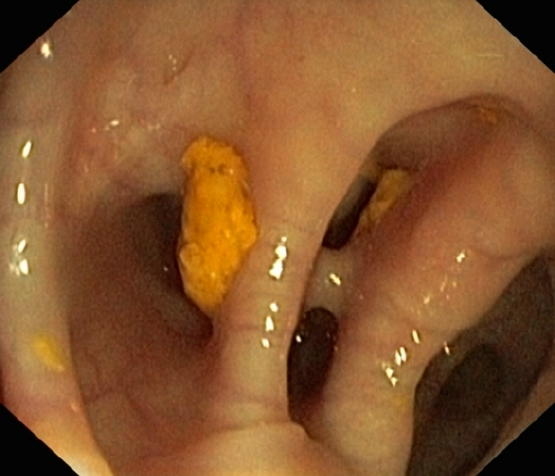

Ein Divertikel bildet sich aus Darmschleimhaut, welche sich durch kleine Lücken der muskulären Darmwand hindurchdrückt. Als Ursache geht man von einer Drucksteigerung im Übergang zwischen Sigma und Rektum (Hochdruckzone des Dickdarms) aus. Diese Divertikel nehmen im Alter zu, bei etwa 60-70% der 70-jährigen Patientinnen und Patienten ist eine sogenannte Divertikulose in der Darmspiegelung zu erkennen. Entzündet sich eines dieser Divertikel, spricht man von einer Divertikulitis. Meist kommt es zu Schmerzen im linken Unterbauch, teilweise begleitet mit Obstipation und Fieber.

Beim erstmaligen Auftreten einer Divertikulitis wird eine Antibiotikatherapie eingeleitet. Oft erfolgt diese, gerade wenn bereits Fieber aufgetreten ist, intravenös und somit stationär. Wenn die Beschwerden rückgängig sind, kann auf Antibiotikatabletten gewechselt werden. Zu diesem Zeitpunkt ist die Therapie auch ambulant möglich. Die Spitalaufenthaltsdauer beträgt meist 2 - 4 Tage. Zur weiteren Diagnostik sollte nach 6 Wochen eine Darmspiegelung durchgeführt werden, um ein Tumorgeschehen sicher auszuschliessen und die Diagnose der Divertikulose nochmals zu bestätigen.